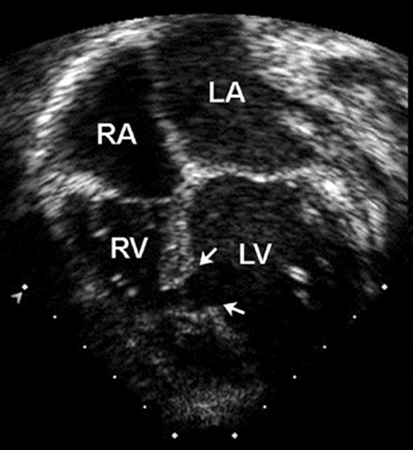

Os defeitos perimembranosos normalmente ocorrem como uma lesão solitária e, às vezes, podem fechar espontaneamente pela aposição do folheto septal da valva tricúspide ao defeito. Os defeitos de saída podem ser grandes e associados a formas mais complexas de cardiopatias congênitas, como a tetralogia de Fallot. Os DSVs de saída ou peri-membranosos estão intimamente próximos da cúspide direita da valva aórtica. Por causa do efeito Venturi, esses defeitos podem causar prolapso de uma cúspide da valva aórtica, o que resulta em uma restrição do fluxo através do DSV e regurgitação da valva aórtica.[22] Os defeitos de entrada não se fecham espontaneamente e podem estar associados com o defeito do septo atrioventricular (DSAV) e com a regurgitação da valva AV. Os defeitos musculares são os tipos mais comuns de DSVs em neonatos e a grande maioria fecha espontaneamente antes dos 2 anos de idade.[Figure caption and citation for the preceding image starts]: Imagem da ecografia apical de 4 câmaras de um defeito do septo ventricular (DSV) muscular (seta). (AD) átrio direito; (AE) átrio esquerdo; (VD) ventrículo direito; (VE) ventrículo esquerdoImagem cedida por Patrick W. O'Leary, MD [Citation ends].